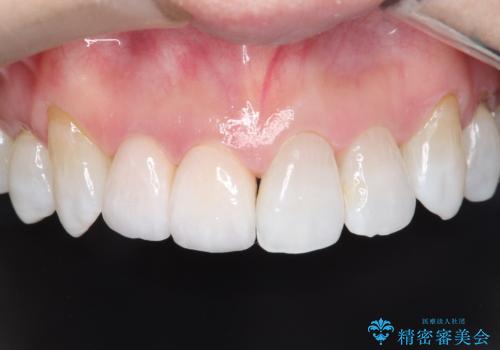

歯と歯の間の虫歯もセラミックで再発防止

- 左上6番の奥歯のコンタクト下カリエス(歯と歯の間の虫歯)を主訴にご来院されました。レントゲンと精密診査の結果、歯と歯の間という、再発しやすい部位の虫歯であることが判明。患者様のご希望と口腔内の状態を考慮し、虫歯を徹底的に除去し、精密で再発リスクの低いセラミッククラウンで修復する治療計画を立案しました。これにより、見た目の美しさだけでなく、長期的な歯の健康維持を目指します。

治療では、まず虫歯に侵された歯質を丁寧に除去し、セラミッククラウンを装着するための歯の形成を行いました。型取りから患者様の歯の形や色に合わせたオーダーメイドのセラミッククラウンを作製。セラミックは、隣接する歯との隙間なく精密に適合し、プラークが付着しにくいため、虫歯の再発を防ぐ効果があります。最終的に、精度の高いクラウンを装着し、咬み合わせを細かく調整しました。これにより、虫歯の再発を防ぎ、快適に食事ができる奥歯を取り戻していただけました。